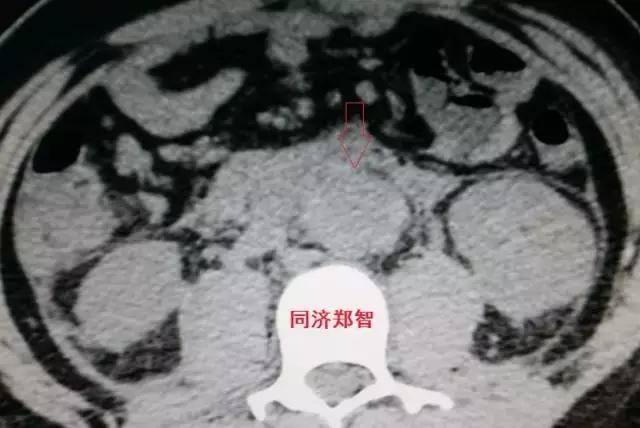

病例四

腹部平扫CT提示腹主动脉增宽,CTA证实为腹主动脉局限性夹层(红箭头所示)。